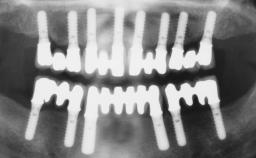

Conventional Loading of Eight Implants in the Maxilla and Final Restoration with a Full-Arch Gold-Ceramic FDP

# of Implants 8

Defining Characteristics Fully edentulous upper jaw to be rehabilitated with four or more implants

Modality Fixed hybrid bridge on 5+ implants

Bone Volume Deficient vertically or deficient vertically AND horizontally